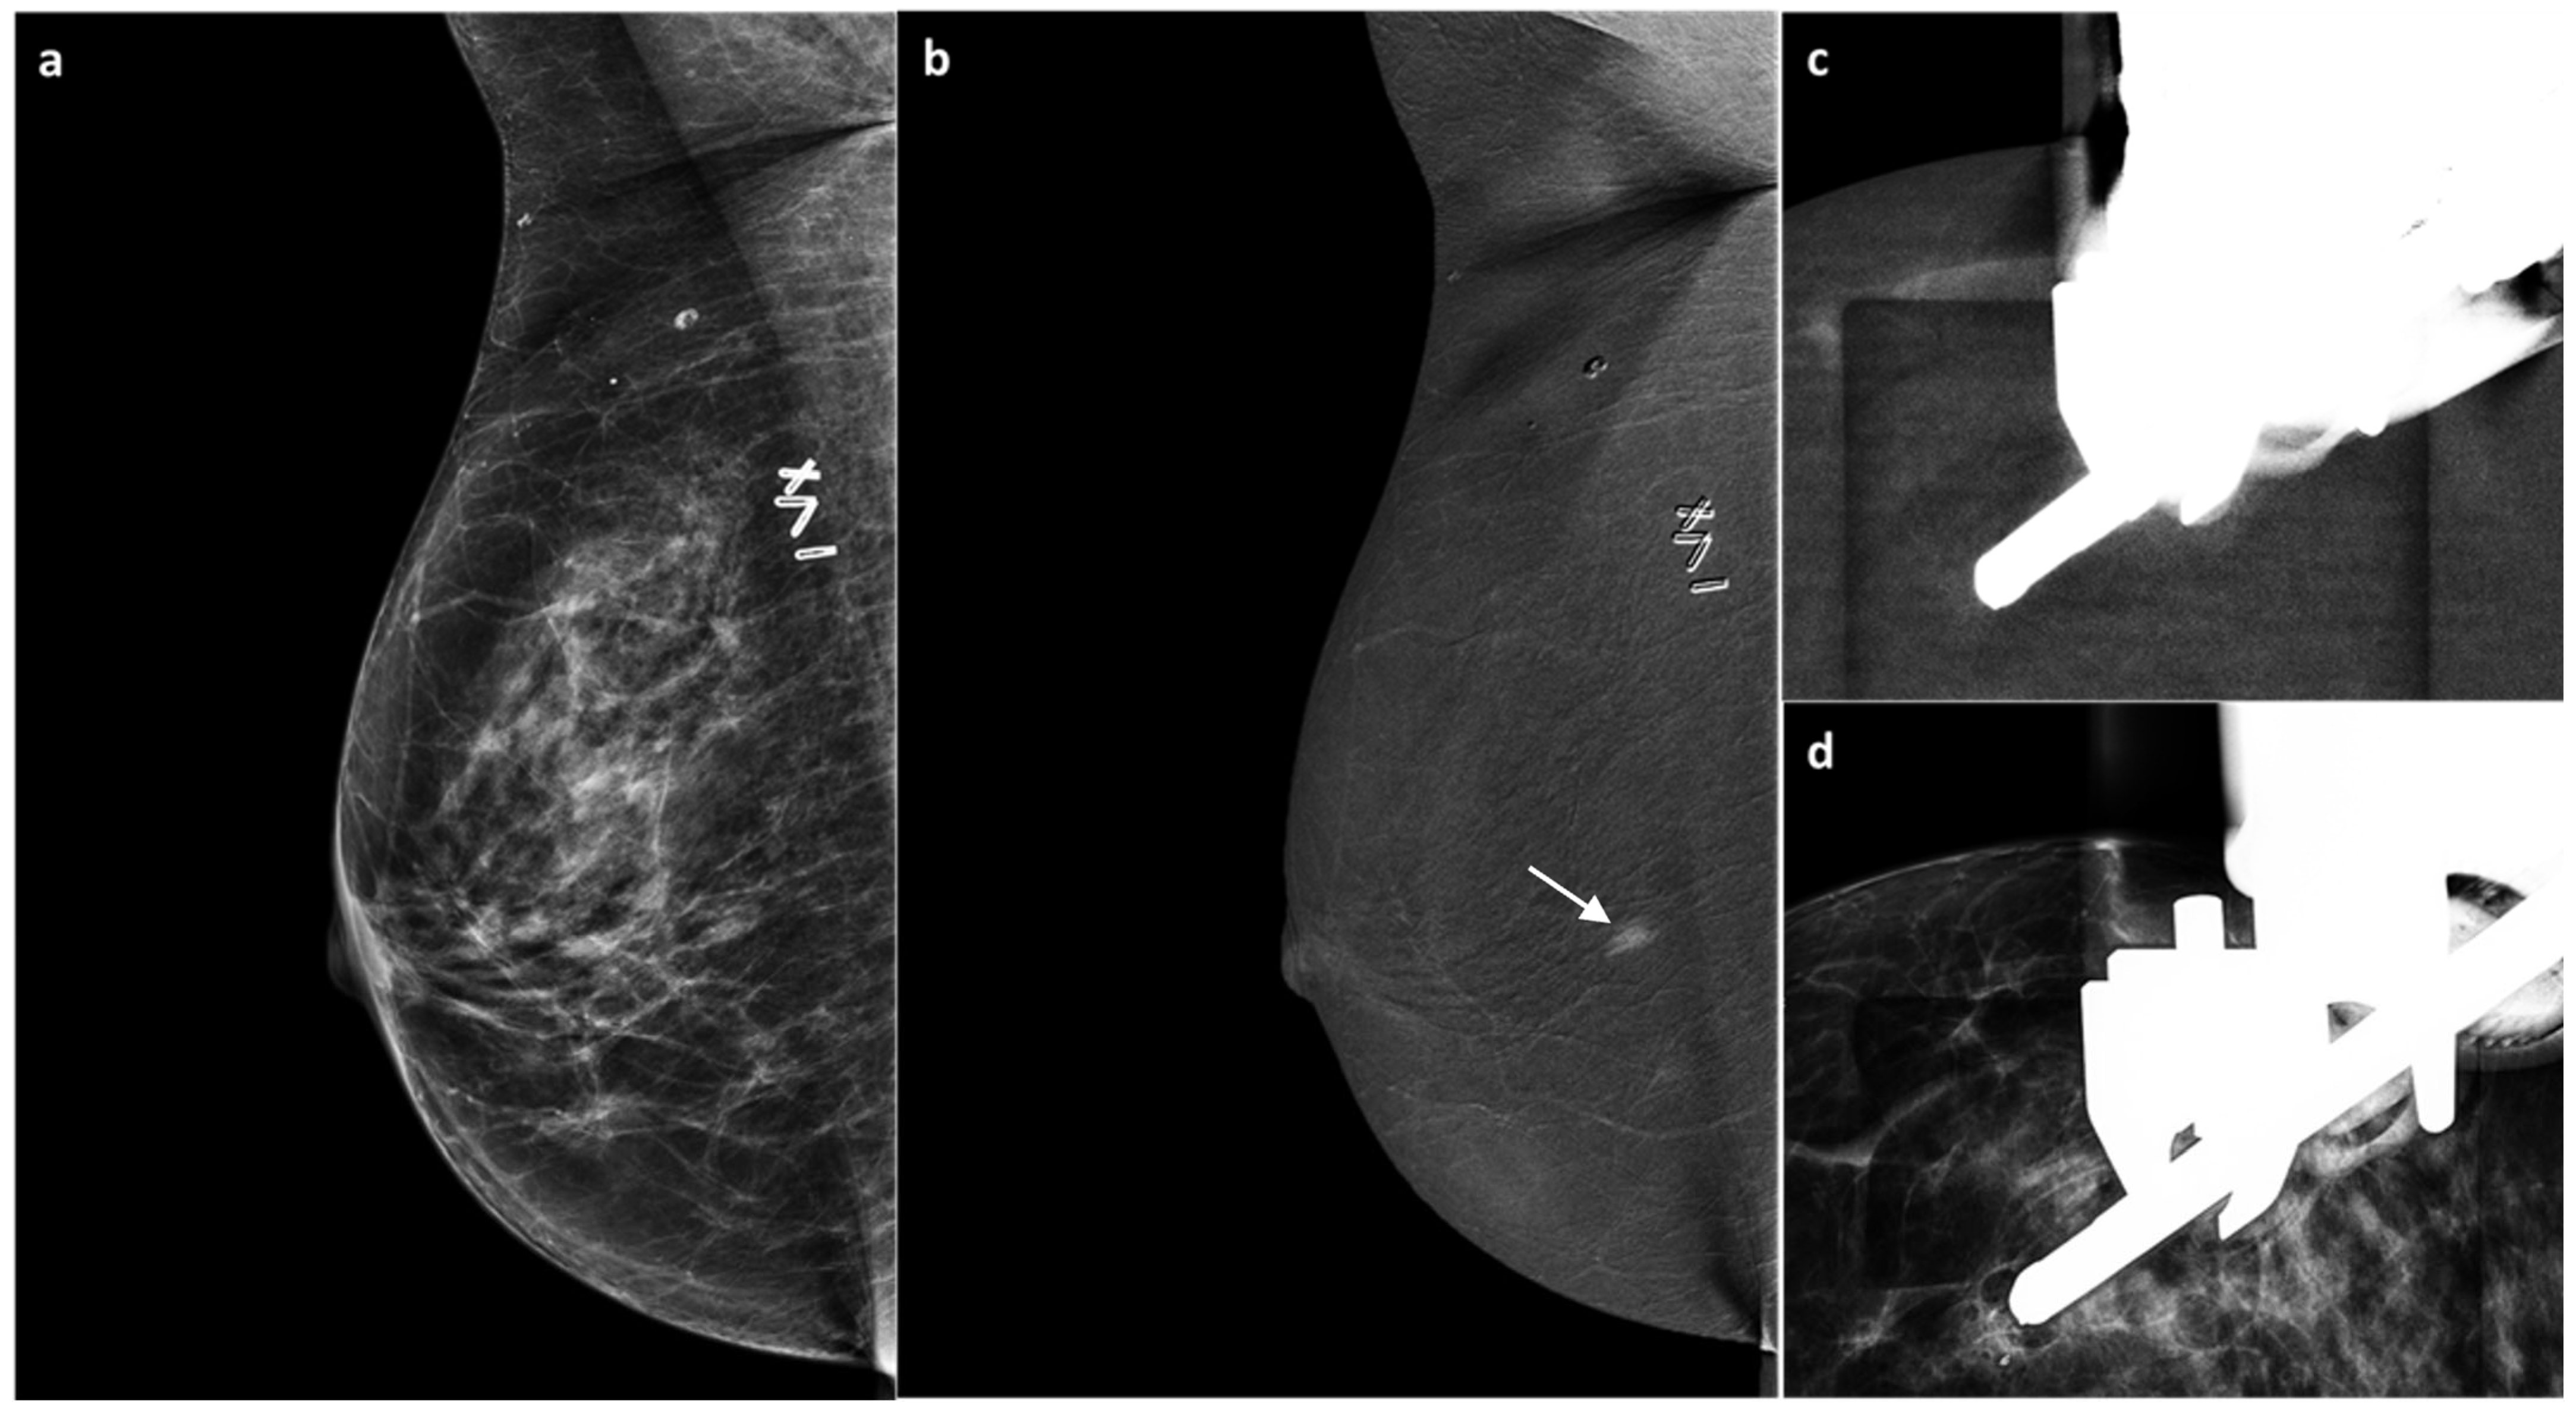

3.2. CEM Examination and Analysis